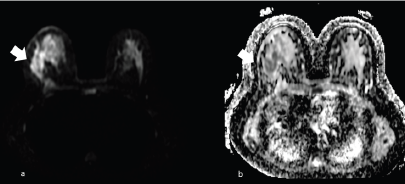

Magnetic resonance imaging using T2-weighted images may show granulocytic sarcoma as ill-defined, heterogeneous, hyperintense masses relative to breast parenchyma, and hypointense on T1 images (Figure 5), inhomogeneous enhancement (Figure 6) on gadolinium administration and restricted diffusion (Figure 7).

Figure 7. The same patient of Figure 6, showing right unilateral breast mass, subsequently identified as a MS. (a): Diffusion imaging with hyperintense mass (arrow) and (b): the restricted diffusion of the same mass (arrow) in the apparent diffusion coefficient (ADC) mass.